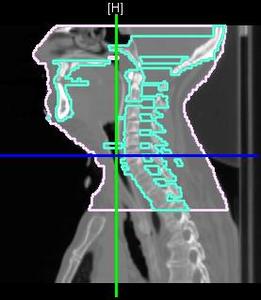

Our previous contributions to the ITK community include a generalized B-spline approximation scheme as well as a generalized information-theoretic measure for assessing point-set correspondence known as the Jensen-Havrda-Charvat-Tsallis (JHCT) divergence. In this submission, we combine these two contributions for the registration of labeled point-sets. The transformation model which uses the former contribution is denoted as directly manipulated free-form deformation (DMFFD) and has been used for image registration. The information-theoretic approach described not only eliminates exact cardinality constraints which plague exact landmark matching algorithms, but it also incorporates the local point-set structure into the similarity measure calculation. Although theoretical discussion of these two components is deferred to other venues, the implementation details given in this submission should be adequate for those wishing to use our algorithm. Visualization of results is aided by another of our previous contributions. Additionally, we provide the rudimentary command line parsing classes used in our testing routines which were written in the ITK style and also available to use consistent with the open-source paradigm.